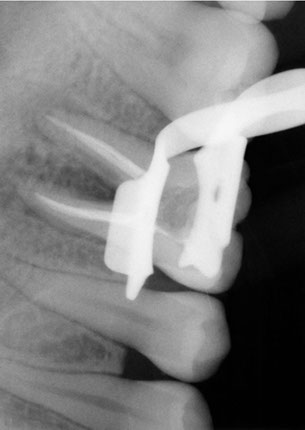

Durante un procedimiento de conducto radicular, o endodoncia el nervio y la pulpa se eliminan y el interior del diente se limpia, se empasta la raíz con los materiales correspondientes y se procede a la reconstrucción de la corona dental, todo éste tratamiento se realiza habiendo aplicado anestesia local en la zona afectada, la misma anestesia que se utiliza para un simple empaste o una extracción.

La endodoncia le da más tiempo de vida útil a su pieza dental, en Dental Evolution Cancún le recomendamos evitar la extracción realizándose este procedimiento que garantizamos será sin dolor, gracias a la tecnología de vanguardia con la que contamos, instrumental rotatorio, sistema de ultrasonido, y a nuestra “radiografía digital” la cual juega un papel crucial en el procedimiento de endodoncia, además de que usted estará atendido con la calidez, calidad humana y profesionalismo que caracteriza a nuestro experto equipo de dentistas especializados que le apoyaran en todo momento.